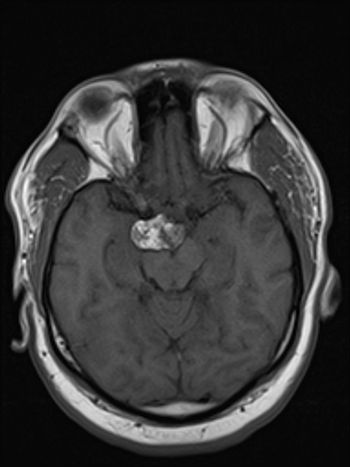

46-year-old male presents with headache.